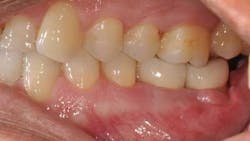

Ten months after the GBR procedure was done, a new panoramic radiograph (Fig. 4) was taken and the site was reentered for implant placement into an ideal restorative position. Dental implants (nobel active 5.0 x 11.5 mm) were placed at the No. 18 and No. 19 positions (Fig. 5), into excellent type I dense bone; note that the majority of the dental implants are completely housed in newly grafted bone. Additional minor bone grafting was done using autogenous coagulum collected during the osteotomies and a xenograft particulate (Bio-Oss, Geistlich), then covered with a resorbable collagen membrane (Biogide, Geistlich) in order to maintain buccal bone stability and contour (Fig. 6). The implants were later uncovered, ensuring that an adequate zone of keratinized tissue was present and the implants were subsequently restored (Figs. 7, 8). The success of this case was dependent upon proper treatment planning, meticulous surgical techniques, patient compliance, and understanding bone and soft-tissue biology.

Fig. 7

Fig. 8